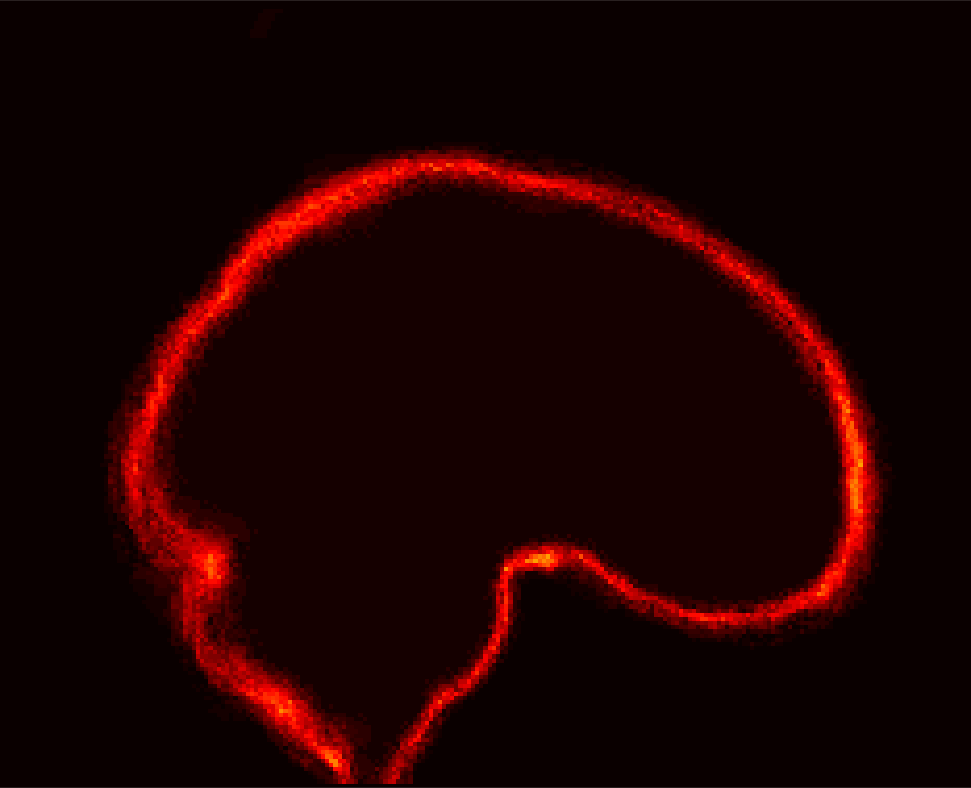

[Uncaptioned image] [Uncaptioned image] [Uncaptioned image] [Uncaptioned image]

(a) (b) (c) (d)

Figure 8: Example BRATS image with its decomposition result in atlas space. (a) Input image after pre-processing; (b) quasi-normal image L+M𝐿𝑀L+M; (c) non-brain image S𝑆S; (d) pathology image T𝑇T.

In addition to extracting the brain from pathological datasets, our method also allows for the estimation of a corresponding quasi-normal image in atlas space, although this is not the main goal of this paper. Fig.8 shows an example of the reconstructed quasi-normal image (L𝐿L) for an image of the BRATS dataset, as well as an estimation of the pathology (pathology image T𝑇T and non-brain image S𝑆S). Compared to the original image, the pathology shown in the quasi-normal image has been greatly reduced. Hence this image can be used for the registration with a normal image or a normal atlas. This has been shown to improve registration accuracy for the registration of pathological images [27]. Furthermore, an estimate of the pathology (here a tumor) is also obtained which may be useful for further analysis. Note that in this example image the total variation term captures more than just the tumor. This may be due to inconsistencies in the image appearance between the normal images (obtained from OASIS data) and the test dataset. As our goal is atlas alignment rather than quasi-normal image reconstruction or pathology segmentation, such a decomposition is acceptable, although we could improve this by tuning the parameters or applying regularization steps as in [27].